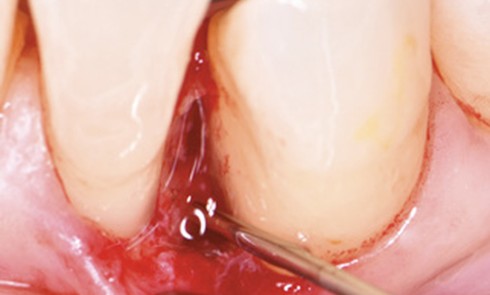

Article réservé à nos abonnés Régénération d’une lésion intra-osseuse par approche chirurgicale minimalement invasive

Résumé La prise en charge des maladies parodontales débute par le contrôle des facteurs de risques systémiques et locaux modifiables. À...